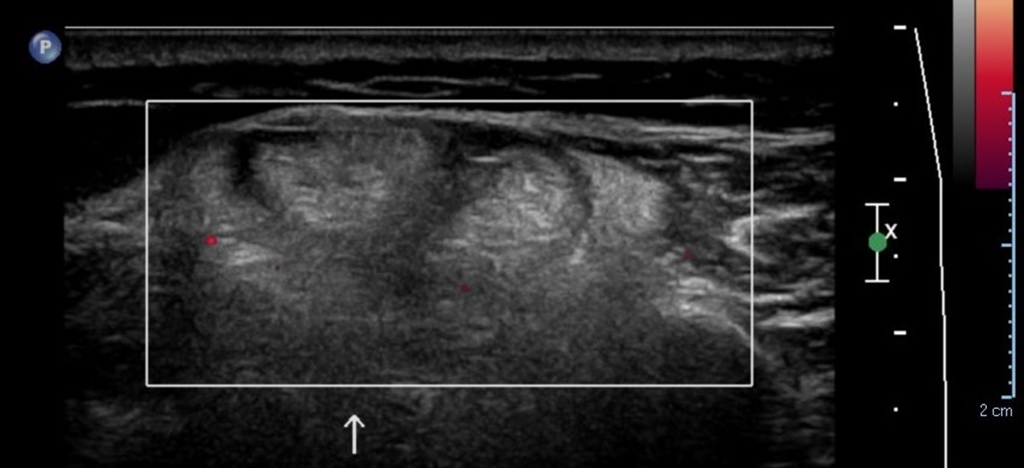

• En musculo deltoides, a nivel de fascículos medio y posterior, aumento de volumen a nivel intramuscular, palpable, con área hiperecogénica heterogénea y perdida de patrón fibroadiposo, sin señal al Doppler color. En la relación a sintomatología (sobrecarga de trabajo), hallazgo en probable contexto de desgarro. Probable diagnostico diferencial Neoplasia intramuscular sugerente de lipoma.

• En músculo deltoides, a nivel de fascículos medio y posterior se observa área aumento de volumen a nivel intramuscular, palpable, con pérdida de patrón fibroadiposo, sin señal al doppler color, el área mide 3,6 x 13 cm.

Impresión: Hallazgos en probable contexto de DOMS muscular, el diagnóstico diferencial plantea lipoma intramuscular lo cual es menos probable.